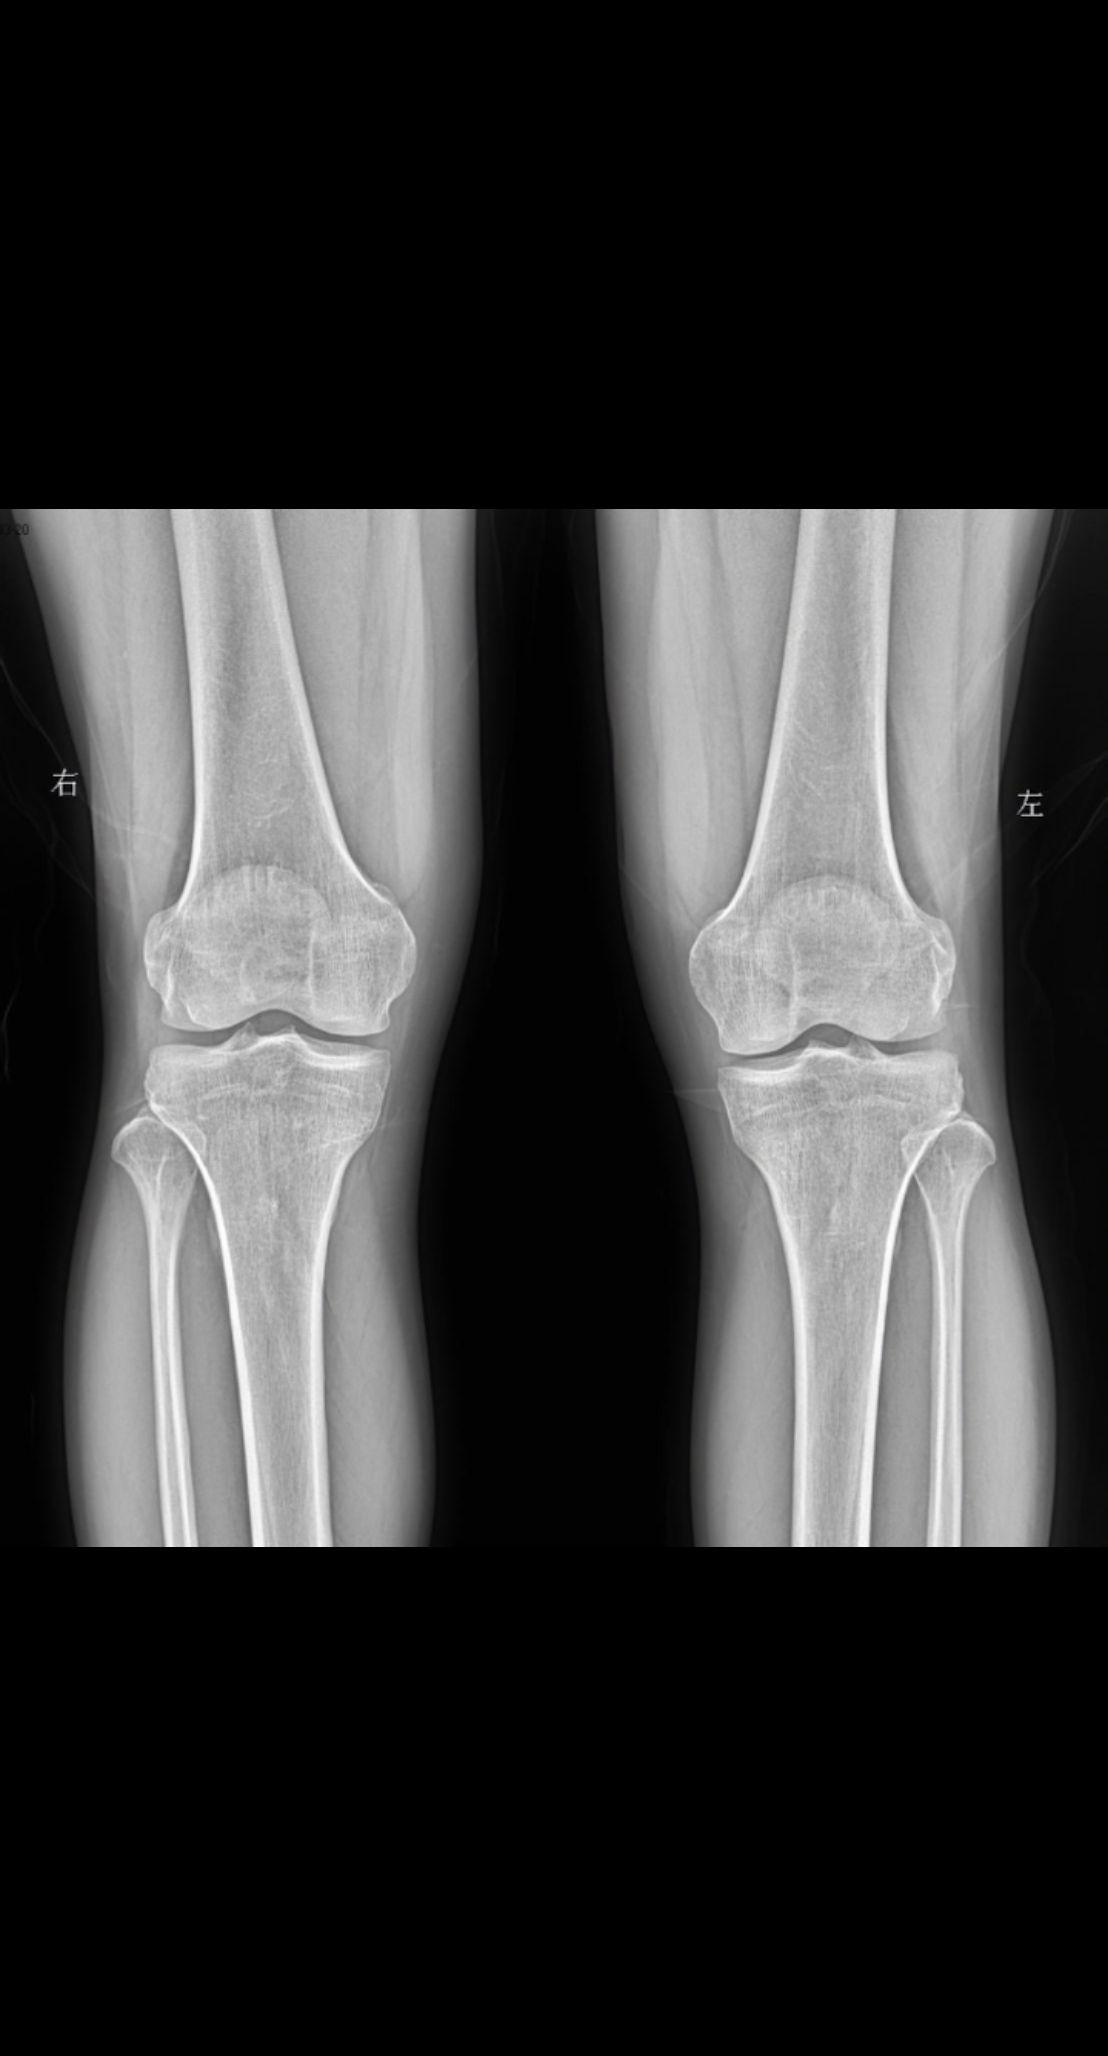

老师们拍摄膝关节采取站立位还是卧位

2025-05-22 01:35

主诉 患者右侧膝盖疼痛 男47

2025-03-20 16:38